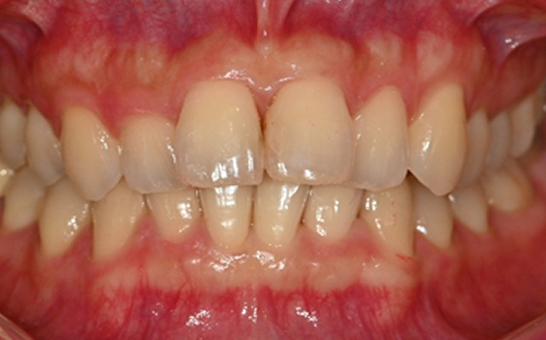

※ 바른선택치과의원은 의료법을 준수하며 위 케이스는 실제 내원 환자분의 동의하에 공개된 사진과 동일한 환자분께 같은 조건에서 촬영한 사진을 활용했습니다.

개인에 따라 진료 및 치료 방법이 다르게 적용할 수 있으며, 효과와 부작용이 개인마다 다르게 나타날 수 있는 점을 안내해 드리며, 진료 전 전문의료진과 충분한 상담을 권해드립니다.